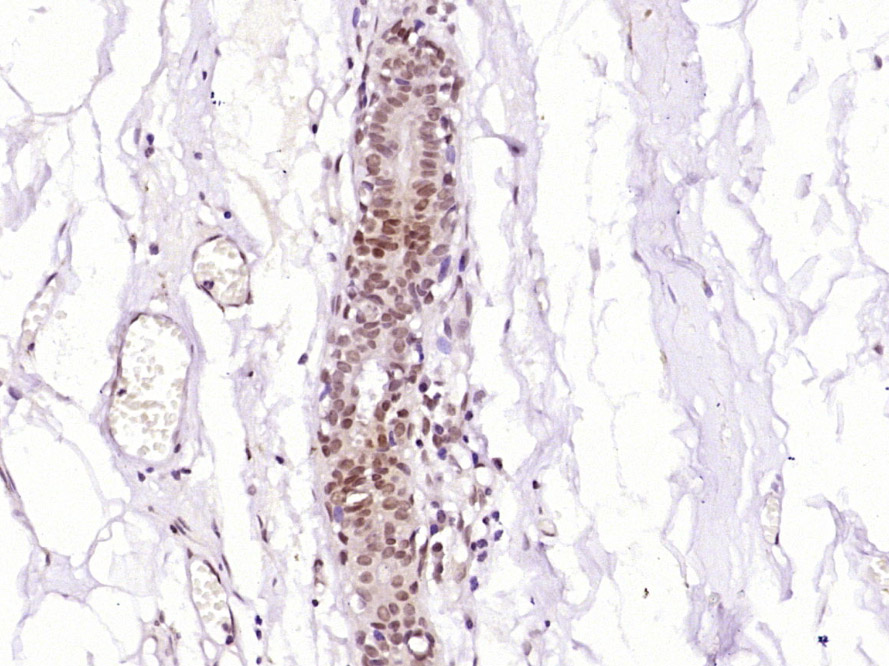

| 英文名称 | MDFI Rabbit pAb |

| 中文名称 | 抑制肌原调节蛋白1抗体 |

| 产品应用 | IHC-P=1:100-500, IHC-F=1:100-500, IF=1:100-500 Not yet tested in other applications. |

| 交叉反应 | Human (Mouse, Rat, Pig, Cow, Horse, Sheep) |

| 亚细胞定位 | Nucleus. Cytoplasm. |

| {IHC-P} | {1:100-500} |